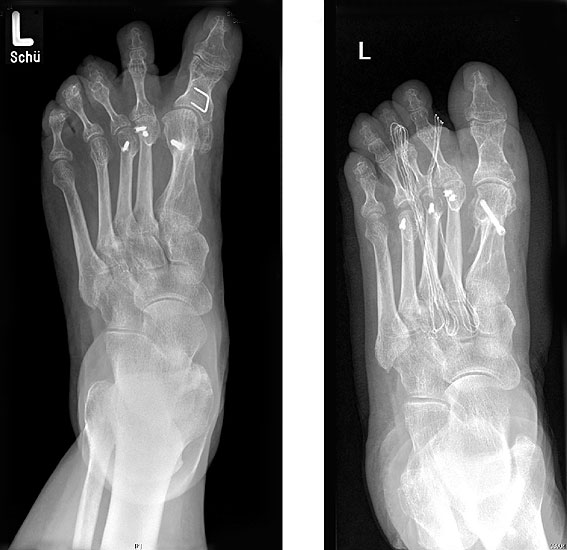

Radiologische Diagnostik

11"> Der Hallux varus Winkel  <a class=11" title="Der Hallux varus Winkel 11" srcset="/assets/images/2/4-vk3bypbg5s5x7zc.jpg 1x, /assets/images/3/4-aax2sd1hrpnrvrb.jpg 1.452x" width="270" height="240" loading="lazy">

Abbildung 3

Die bildgebende Diagnostik hilft bei der Klärung der Ätiologie und des Ausmaßes der Fehlstellung. Hierzu sind Röntgen­aufnahmen im Stand in mindestens zwei Ebenen unter Belastung des Fußes erforderlich. Mit Hilfe der belasteten Röntgenaufnahmen wird der Hallux-varus-Winkel, d. h. den Winkel zwischen der Achse der Grundphalanx der Großzehe und der Achse des ersten Mittelfußknochens bestimmt, sowie etwaige Rotationsfehlstellungen des 1. Strahls verifiziert. Eventuelle knöcherne Fehlanlagen bei kongenitalen Deformitäten können hierdurch ebenfalls verifiziert werden.

Weitere Beurteilungskriterien sind:

• degenerative Veränderungen des MTP I

• Kongruenz des MTP I- Gelenkes

• Form und Stellung des Mittelfußköpfchens I

• Ausprägung der Pseudoexostose.

• PASA-Winkel, d. h. der periphere Artikulationswinkel des Großzehengrundgelenkes.

Zur Klärung der Ätiologie wird der intermetatarsale Winkel zwischen Os metatarsale I und II bestimmt. Ist dieser kleiner als 5° oder gar negativ, ist eine Varusstellung der Großzehe oft die Folge.

Am Röntgenbild des belasteten Fußes bestimmt man die Lage der Sesambeine zum 1. Mittelfußköpfchen.

Anhand der Röntgenaufnahme lassen sich die Folgen einer eventuellen Voroperation bestimmen, wie z. B. die Stellung des ersten Mittelfußköpfchens, des ersten Metatarsale nach Korrekturen der Achse bei einer Hallux-valgus-Operation. Mitunter bestehen Nekrosen des Mittelfußköpfchens oder eine übermässige Resektionen der Pseudoexostose. Auch die Länge des 1. Metatarsale kann von Interesse sein, z. B. nach einer Lapidusarthrodese (Johnson 1994).